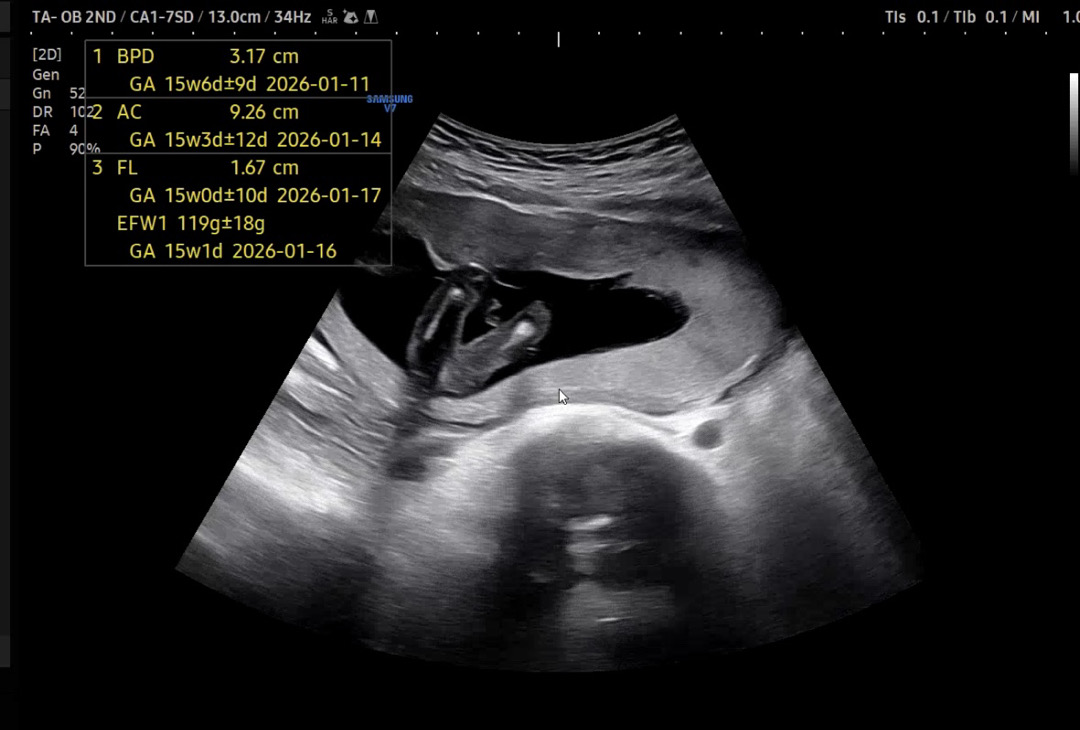

15주 2일차

젠더리빌 하고싶었는데..마침 담주에 가족모임이 있어서 오늘 새로운 병원에 가봤어요.. 진료봤는데 너무 꼼꼼하게 봐주셔서 여쭤보기도 전에 성별을 눈치챘네여ㅎㅎㅎ 내심 딸을 바랐어서.. 반전이 없길!